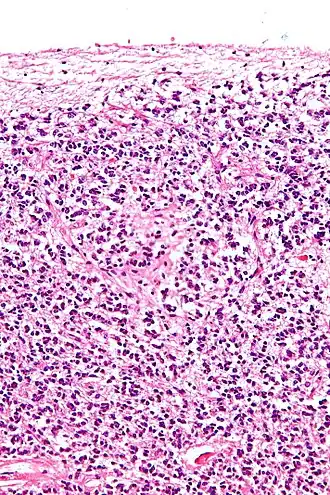

![]() Поперечный разрез шишковидной железы, на котором видны пинеалоциты и другие клетки. |

Пинеалоциты — это основные клетки, содержащиеся в шишковидной железе, расположенной за третьим желудочком и между двумя полушариями головного мозга. Основной функцией пинеалоцитов является секреция гормона мелатонина, важного в регуляции циркадных ритмов(сна). У людей супрахиазматическое ядро гипоталамуса передает пинеалоцитам сигнал темноты и, как следствие, контролирует дневной и ночной цикл[1]. Было высказано предположение, что пинеалоциты происходят из фоторецепторных клеток[2]. Исследования также показали снижение количества пинеалоцитов путем апоптоза с увеличением возраста организма[3]. Существует два разных типа пинеалоцитов, тип I и тип II, которые были классифицированы на основе определенных свойств, включая форму, наличие или отсутствие складчатости ядерной оболочки и состав цитоплазмы.